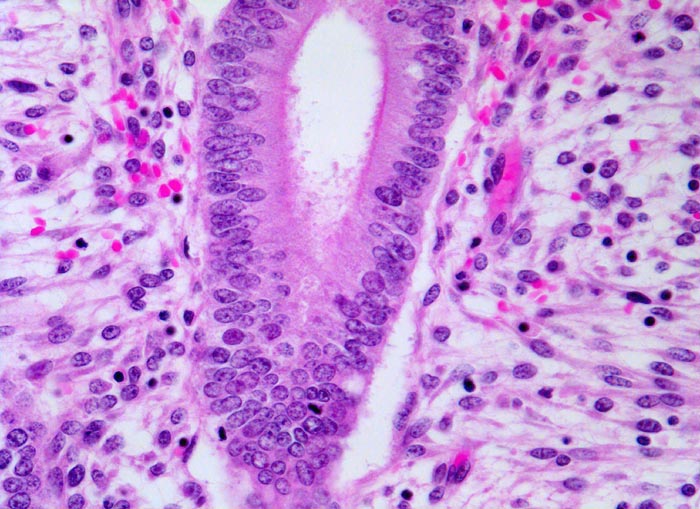

PathoPic ID 4748 - Mittlere Proliferationsphase des Endometriums

Mittlere Proliferationsphase des Endometriums

Normalbefund

Endometrium

Genitalorgane, weiblich

Epithel hochzylindrisch, Kerne länglich chromatinreich mit Mitosen. Stroma aufgelockert.

Uterus myomatosus

Histologie

200

44